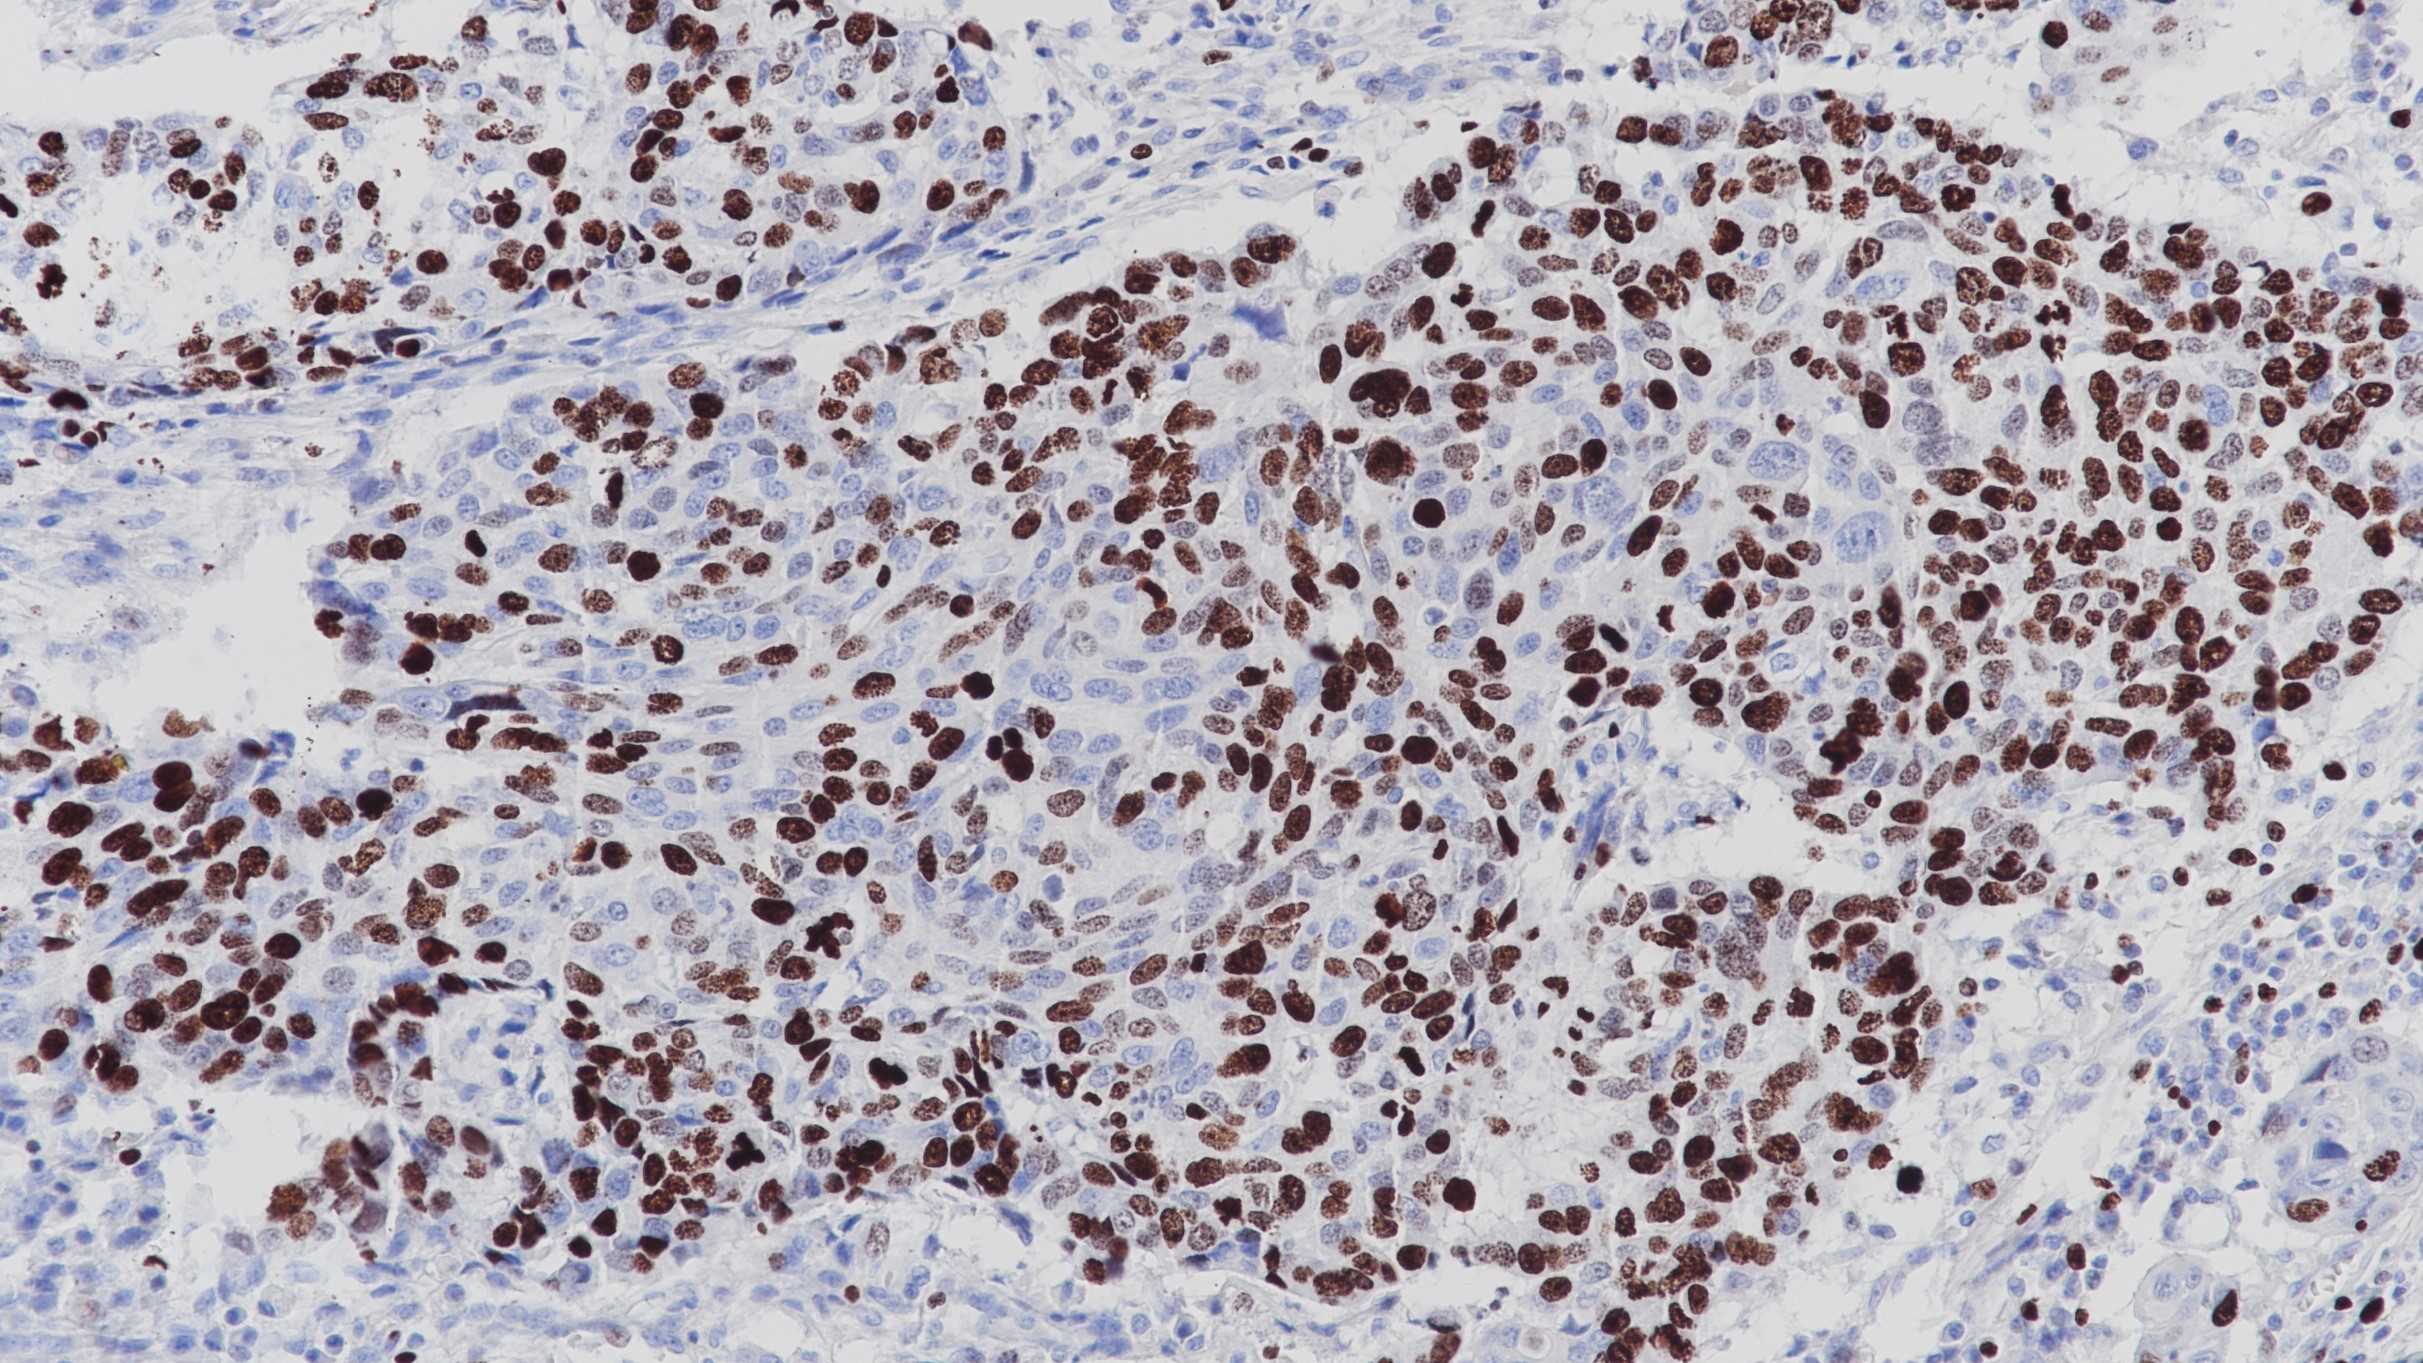

Ki-67 重组兔单克隆抗体

Ki-67抗原是一种与细胞增殖有关的核蛋白,可能是细胞增殖的关键因素。此外,Ki-67还与核糖体RNA转录有关。Ki-67存在于细胞分裂周期G1、S、M和G2期,但在细胞静止期G0期不表达。Ki-67被用作不同类型肿瘤的诊断工具,因为它存在于所有增殖细胞(正常细胞和肿瘤细胞)中,是一种用来确定给定细胞群体增殖比率非常好的标记物。

亚细胞定位

细胞核

阳性对照

扁桃体